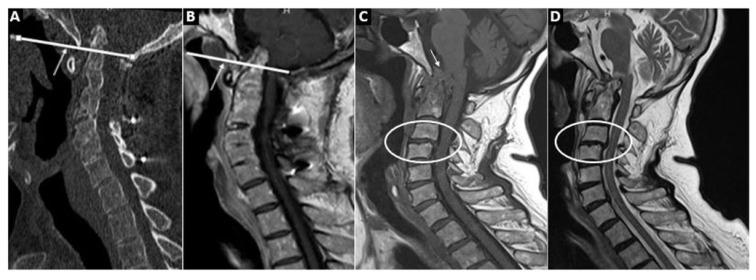

Exactly 459 patients (204 RA, 200 SpA, and 55 PsA) and 78 patients in the control group were included in the study. CCJ involvement was detected in 101 (49.5%) RA, 53 (26.5%) SpA, 10 (18.2%) PsA, and 4 patients (5.1%) in the control group (p < 0.001). The odontoid process was one of the main targets, especially in RA patients (69 (33.8%)), which was significantly higher than in the SpA, PsA, and control groups. Although vertical subluxation (VS) was numerically higher in the RA and SpA groups compared to the control group, VS-related brainstem compression was relatively uncommon: 6 (2.9%) in RA, 1 (0.5%) in AS, and none in the PsA and control groups.

共纳入 459 例患者(204 例 RA、200 例 SpA 和 55 例 PsA)和 78 例对照组患者。RA、SpA、PsA 和对照组患者中分别有 101 例(49.5%)、53 例(26.5%)、10 例(18.2%)和 4 例(5.1%)存在 CCJ 受累(p < 0.001)。齿状突是主要的受累部位之一,尤其是在 RA 患者中(69 例,33.8%),明显高于 SpA、PsA 和对照组。虽然 RA 和 SpA 组的垂直半脱位(VS)数值高于对照组,但 VS 相关的脑干压迫相对少见:RA 组 6 例(2.9%),AS 组 1 例(0.5%),PsA 和对照组均无。